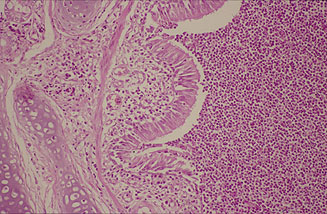

(Fig. 7)

(Fig. 8)

Si el proceso evoluciona hacia la

cronicidad tiene lugar la proliferación de tejido

de granulación alrededor de las zonas de necrosis,

que resultan posteriormente limitadas por una cápsula

de tejido conectivo (Fig. 7).

Estas lesiones contienen un elevado

número de microorganismos, lo que determina un

estado de animales portadores crónicos, pudiendo

tener lugar una exacerbación de los síntomas

y la aparición de complicaciones debidas a la intervención

de otros microorganismos oportunistas. En esta

fase aparecen exudados purulentos en bronquios y bronquiolos

(Fig. 8) y si no se produce

la reabsorción del exudado fibrinoso pleural, éste

evoluciona hacia la fibrosis con formación de sinequias.

En los ganglios linfáticos regionales se observa

linfadenitis purulenta.